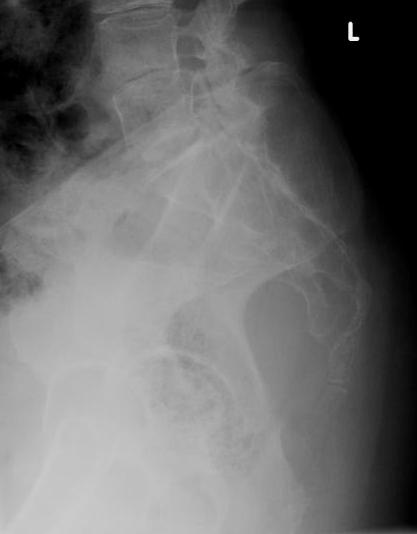

Plain x-ray (Fig. 1-3)

• Midline bone lytic lesion with focus in the vertebral body

• Surrounding soft tissue mass

• Invade intervertebral discs and contiguous vertebras.

Fig. 1-3: Plain X-ray of the sacrum demonstrates a chordoma. There is a lytic lesion of the sacrum with total destruction of the sacrum.